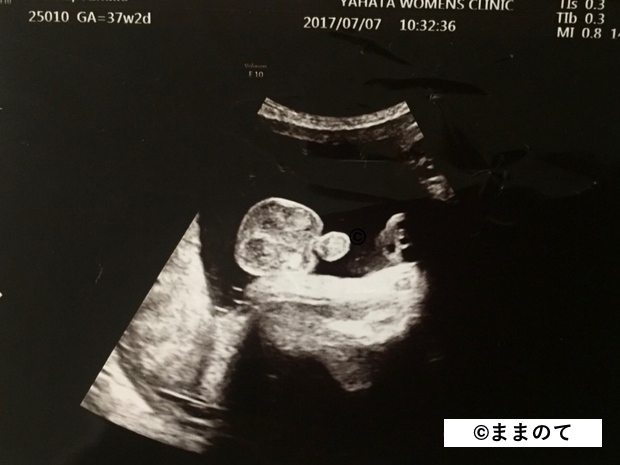

妊娠10ヶ月(36・37・38・39週)

臨月となり、赤ちゃんはいつ生まれてもおかしくない身体に成長しています。エコー写真には存在感のある顔が写ることもありますよ。

身長は約50cm、体重は3,000gが目安ですが、赤ちゃんの成長には個人差があるため、医師から特別な指導がなければ安心して赤ちゃんと対面できるときを待ちましょう。